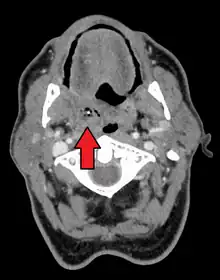

Absceso periamigdalar del lado derecho

Imagen de tomografía axial computarizada con un absceso periamigdalino derecho.